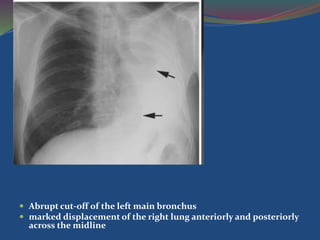

Collapse seen in carcinoma of the bronchus.

 Abrupt cut-off of the left main bronchus

 marked displacement of the right lung anteriorly and posteriorly

across the midline

 Adhesive collapseRespiratory distress syndrome surface tension of alveoli is decreased by surfactant. If this mechanism is disturbed, collapse of alveoli occurs, although the central airways remain patent  Resorption collapse  In acute bronchial obstruction the gases in the alveoli are steadily taken up by the blood in the pulmonary capillaries and are not replenished, causing alveolar collapse. Collapse seen in carcinoma of the bronchus.

 Abrupt cut-offof the left main bronchus  marked displacement of the right lung anteriorly and posteriorly across the midline